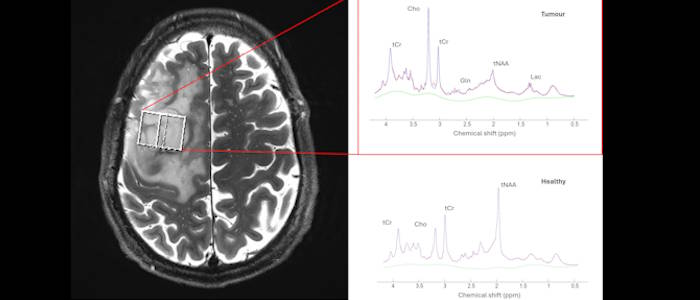

Characterisation of Gliomas with 7T MRI

From Image to Intervention: AI-Powered MRI Biomarkers for Personalized Brain Tumour Care